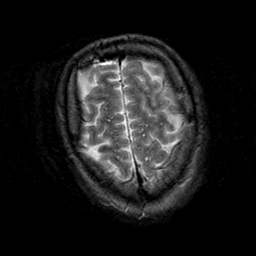

Subacute Stroke, overlay -- Slice #22

[Home][Help][Clinical] Slice 22